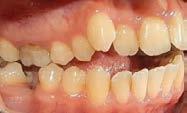

Estudios de inicio intraorales

De frente (Figura 7) presenta líneas medias dentales no coincidentes, 6 mm overjet, 10% overbite, relación molar y canina clase II bilateral. Las oclusales (Figura 8) la arcada superior de forma triangular, presencia de OD 53 y apiñamiento severo, la arcada inferior de forma cuadrada con segundos molares en erupción y apiñamiento moderado.

Figura 5. Corte coronal. Figura 6. Corte sagital. Figura 7. Intraorales de frente, lateral derecha e izquierda. Figura 8. Vista oclusal superior e inferior.